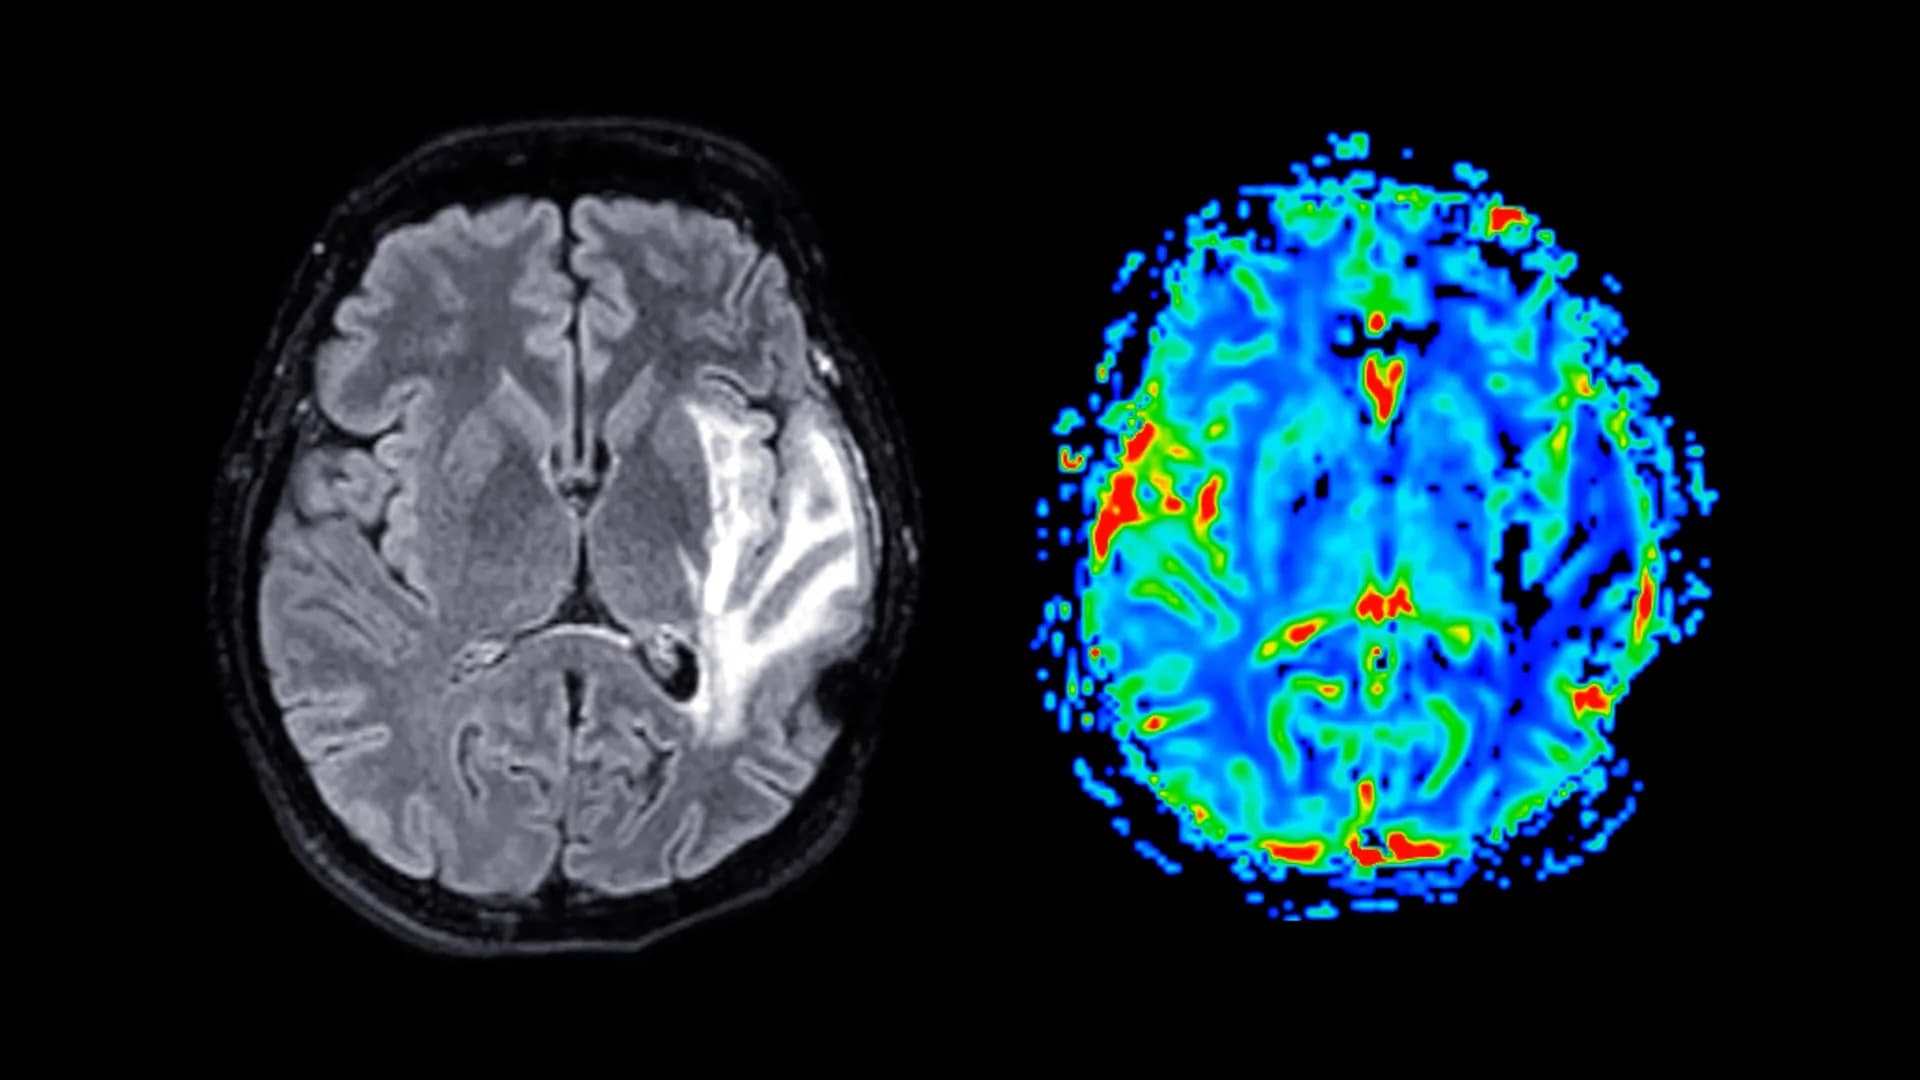

We’ve been fed the narrative that **menopause** is a hot flash and mood swing inconvenience. That narrative just got violently upgraded. New research confirms what whispers have suggested for years: the transition is linked to measurable grey matter loss in key brain regions. This isn't just about memory fog; this is a structural shift happening to half the population during their peak influence years. The target keywords here are **menopause brain fog**, **grey matter loss**, and **midlife women's health**. ### The Cold, Hard Data: Beyond the Anecdote The study, which analyzed brain imaging, reveals that after the final menstrual period, certain areas responsible for executive function and emotional regulation seem to shrink. This validates the lived experience of millions who report cognitive decline. But here is the unspoken truth: **This research is proof of systemic medical neglect.** For decades, research funding and clinical focus have prioritized younger, male physiology. We wait until a problem is statistically undeniable before we even bother to look closely at midlife women's **midlife women's health**. ### Who Really Wins When Women’s Brains Change? Forget the supplement companies for a moment. Who benefits from a generation of highly capable, experienced women facing structural cognitive challenges? The answer is simple: inertia. Institutions, corporate boards, and political structures that are resistant to change thrive when the most experienced demographic—women in their 50s and 60s—are grappling with internal, invisible biological hurdles. This isn't a conspiracy; it’s the predictable outcome of prioritizing one demographic’s health over another’s. The focus on **menopause brain fog** allows the industry to sell quick fixes instead of demanding systemic solutions like subsidized hormone therapy or comprehensive neurological screening post-45. ### The Deep Dive: Estrogen's Ghost in the Machine Estrogen isn't just a reproductive hormone; it's a potent neuroprotectant. Its rapid decline during menopause rips away a crucial shield for the brain. This isn’t just about losing volume; it’s about vulnerability. We are seeing an accelerated aging process in specific cortical regions. Think of it: the moment women often reach the peak of their professional and personal power, their brain architecture becomes structurally less robust. This forces a trade-off: maintain career momentum or prioritize managing severe, biologically induced cognitive load. This is the hidden tax on being a woman in the second half of life. ### What Happens Next? The Prediction We are on the precipice of a massive cultural reckoning regarding **grey matter loss**. Prediction: Within five years, personalized neurological screening for women over 45 will become a major, lucrative sector, driven by consumer demand rather than standard medical protocol. Insurance companies will fight it tooth and nail, classifying it as elective, while high-net-worth individuals demand the best preventative care. The political discourse will eventually shift, forcing increased NIH funding into female-centric neurological studies, but only after the economic cost of lost productivity becomes too high to ignore. We will see the rise of 'Neuro-Hormone Clinics' that treat the brain as the primary organ affected by the menopausal transition. For more on the neurological impact of hormones, see the foundational work on brain plasticity from institutions like the National Institutes of Health (NIH). This is not just a health story; it is an economic and power story masquerading as biology. Ignoring the **menopause brain fog** is no longer an option.Frequently Asked Questions

Studies often highlight regions associated with executive function, memory, and emotional regulation, such as the prefrontal cortex and hippocampus, although specific findings can vary between research groups.